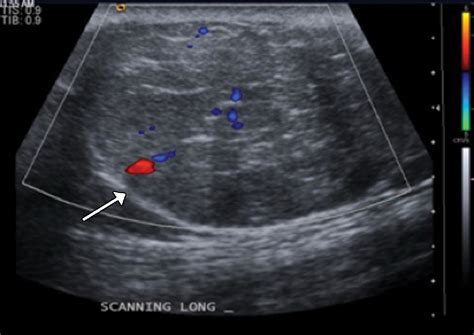

Ultrasound Non-invasive imaging to view soft tissues and identify fluid-filled cysts.

Because the abdomen contains a dense arrangement of structures, relying on a physical "self-exam" is rarely sufficient. A doctor will typically correlate physical findings with diagnostic imaging. For instance, an ultrasound might distinguish between a solid tumor and a fluid-filled cyst, while a CT scan provides the necessary detail to assess whether the mass in stomach involves surrounding blood vessels or lymph nodes. In some cases, a biopsy—the removal of a small tissue sample—is the only definitive way to characterize the cellular nature of the mass.